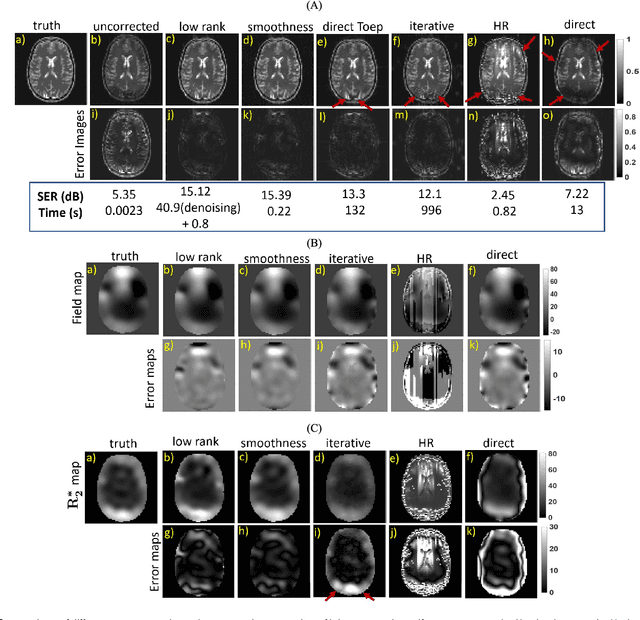

Abstract:We introduce a structured low rank algorithm for the calibration-free compensation of field inhomogeneity artifacts in Echo Planar Imaging (EPI) MRI data. We acquire the data using two EPI readouts that differ in echo-time (TE). Using time segmentation, we reformulate the field inhomogeneity compensation problem as the recovery of an image time series from highly undersampled Fourier measurements. The temporal profile at each pixel is modeled as a single exponential, which is exploited to fill in the missing entries. We show that the exponential behavior at each pixel, along with the spatial smoothness of the exponential parameters, can be exploited to derive a 3D annihilation relation in the Fourier domain. This relation translates to a low rank property on a structured multi-fold Toeplitz matrix, whose entries correspond to the measured k-space samples. We introduce a fast two-step algorithm for the completion of the Toeplitz matrix from the available samples. In the first step, we estimate the null space vectors of the Toeplitz matrix using only its fully sampled rows. The null space is then used to estimate the signal subspace, which facilitates the efficient recovery of the time series of images. We finally demonstrate the proposed approach on spherical MR phantom data and human data and show that the artifacts are significantly reduced. The proposed approach could potentially be used to compensate for time varying field map variations in dynamic applications such as functional MRI.